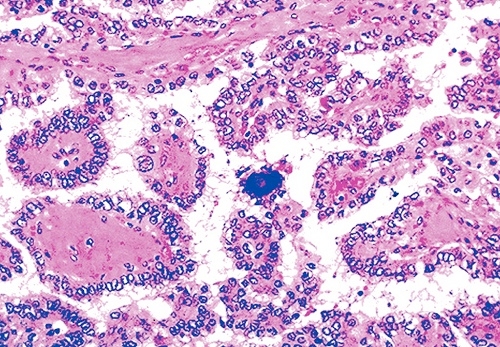

Ung thư tuyến giáp là bệnh lý ác tính ở tuyến giáp, thường gặp ở nữ giới, trên 40 tuổi. Trong các dạng ung thư biểu mô tuyến giáp thì ung thư tuyến giáp thể nhú thường gặp nhất chiếm 80% ung thư tuyến giáp. K tuyến giáp dạng nhú thường diễn biến chậm. Các loại carcinôm dạng nhú biệt hoá kém có diễn tiến nhanh hơn.

Trong các dạng ung thư biểu mô tuyến giáp thì ung thư tuyến giáp thể nhú thường gặp nhất